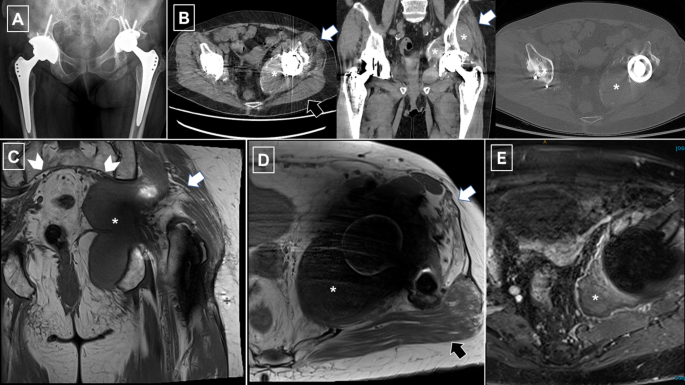

腰椎影像学检查及感染或炎症性疾病排查均未发现异常。血清钴水平升高(66 nmol/L,参考范围<20 nmol/L)。髋关节X光片、腰骶丛神经MRI以及骨盆和左侧髋关节CT显示左侧髋关节周围有一个大的钙化肿块,与髋关节置换术有关,在MRI上T1和T2图像中呈低信号,肿块向内侧和下方延伸至坐骨大切迹,压迫左侧臀中肌和臀小肌,导致这些肌肉萎缩(见图1)。

(A)骨盆正面X光片显示双侧髋关节假体位置正常,无并发症。(B)软组织和骨骼窗口下的轴向及冠状CT扫描显示假体内侧和上外侧有一个病变(星号标记)。病变内侧可见钙化灶。左侧臀中肌和臀小肌萎缩,并伴有脂肪浸润(白色箭头所示),而臀大肌(黑色箭头)未受影响。(C)T1加权冠状MRI图像显示左侧髋关节周围有一个等信号肿块,压迫左侧臀上神经;右侧臀上神经正常(锯齿状阴影)。肿块向下压迫左侧坐骨神经,左侧臀肌部分脂肪萎缩。(D)轴向质子密度图像和(E)增强后的T1加权脂肪饱和度图像显示左侧臀中肌和臀小肌萎缩。低信号肿块因左侧髋关节假体的磁化伪影而部分显示不清,但可见周围组织对比增强。